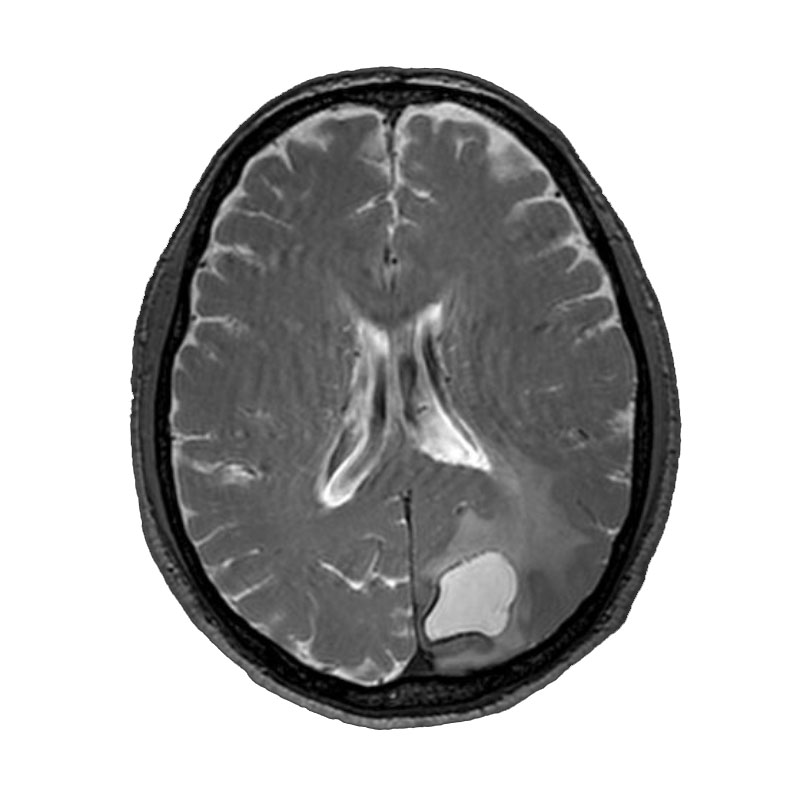

脳動静脈奇形

血管塞栓術

松田/濵田/元永